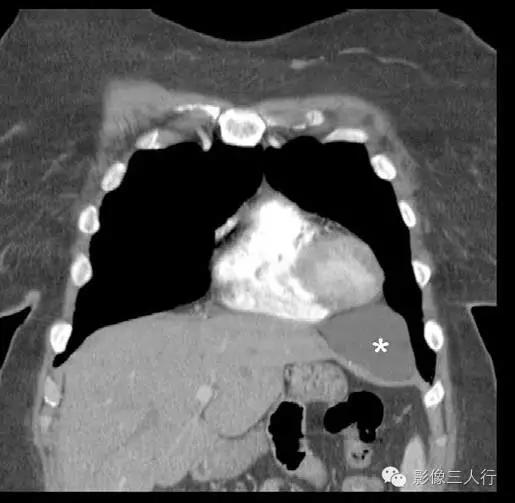

影像表现心包囊肿是一种先天性病变,是心包在早期发育期形成断口的部分所致。心包囊肿可发生于纵隔内的任何部位,但最常见于心膈角。在CT上,典型的心包囊肿无分隔,薄壁甚至不能发现(图1)。对比剂增强后不强化(图2和图3)。心包囊肿通常为水密度,密度可较高,但罕见。在这些病例中,MRI常有助于确定病变的液体性质。囊肿通常在T1加权成像上呈低到中等 信号强度,但在囊肿内含蛋白物质的病例的T1加权成像可呈高信号。囊肿在T2加权成像上呈均匀高信号强度。

图2:胸部增强CT显示右侧心膈角心包囊肿(*)。未见囊肿壁且不强化

图3:胸部增强CT冠状位重组像显示左侧心膈角心包囊肿(*)